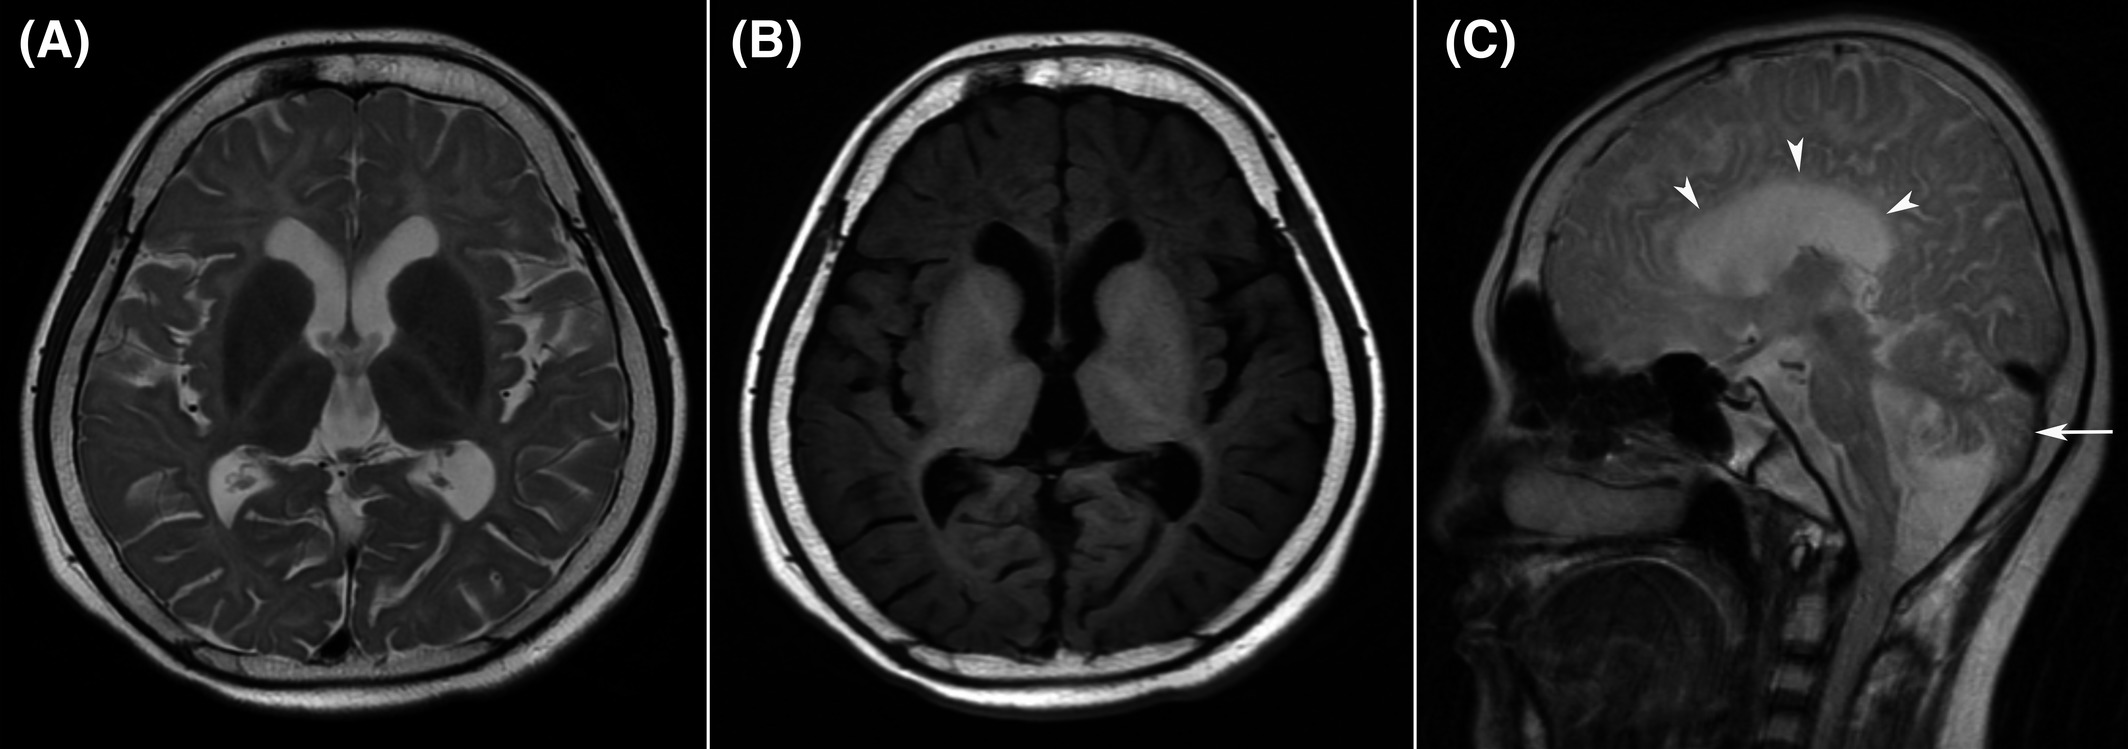

Standard adult head phantom with brain parenchyma, CSF, skull, and ventricles